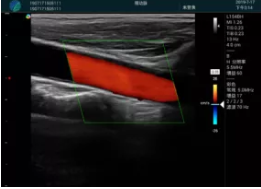

可視化甲狀腺穿刺引導(dǎo)

頸動脈血流充盈飽滿,無外溢

肝內(nèi)血管顯示清晰,血流敏感無外溢

2001年美國健康護(hù)理研究和質(zhì)量監(jiān)督局(AHRQ)批準(zhǔn)了一項(xiàng)關(guān)于提高患者安全性的報(bào)告,建議:在頸內(nèi)靜脈中心置管術(shù)時(shí)使用超聲引導(dǎo)。此后超聲引導(dǎo)穿刺被用于幾乎所有的急診穿刺操作,尤其是血管穿刺。

便攜超聲在急診穿刺中的應(yīng)用:

* 提高了穿刺成功率

* 減少了穿刺損傷及并發(fā)癥

* 縮短了操作時(shí)間

* 減輕了患者痛苦